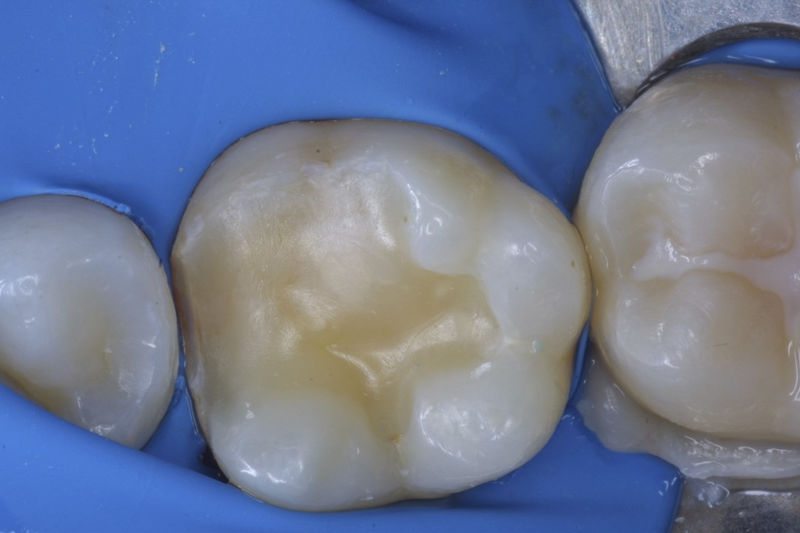

Restauraciones fabricadas en el laboratorio con materiales estéticos, los cuales cubren de manera parcial dientes posteriores. Se utilizan primariamente para restaurar dientes con caries, fracturas y/o defectos amplios. Para poder enviar el caso al laboratorio se toman impresiones utilizando materiales de impresión o técnicas modernas digitales.